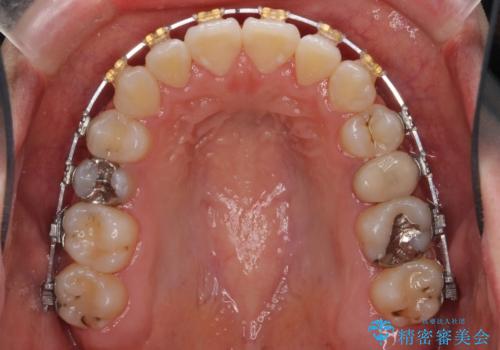

- 矯正装置

- 審美装置

- 治療期間

- 3年2ヶ月

下の小臼歯を抜歯しましたが、その代わり下の親知らずを残して咬ませたので、歯の数は変わっていません。

ただし、左下の親知らずを残すには厚みのある歯ぐきを処置しています。(ディスタルウェッジ)

左上奥歯は、矯正後セラミックインレー修復を行なっています。